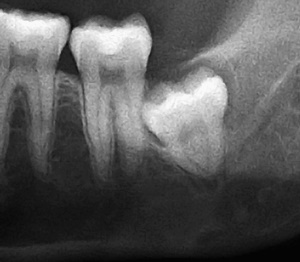

사랑니란?

우리가 사랑니라고 부르는 것은 큰 어금니 중 세 번째 위치에서 제일 마지막에 나오는 치아입니다. 사랑니가 나올 때에는 첫사랑을 하듯이 아프다고 하여 붙여진 이름이라고 하는데요. 다른 이름으로는 ‘지치’라고 합니다. 지치는 사리를 분별할 수 있는 지혜가 생긴다는 뜻입니다.

사랑니는 보통 큰 어금니와 비슷하게 생겼습니다. 사랑니의 형태나 크기는 매우 다양하다고 하는데요. 보통의 어금니 보다 깊이 나기 때문에 빼기 어렵거나 절개를 통해 힘들게 빼야 하는 경우가 많습니다. 원래 사랑니는 음식물을 갈아 내기 위한 용도라고 하는데요. 이것은 치아의 퇴화 현상이라고 생각하시는 분들도 많이 계십니다.